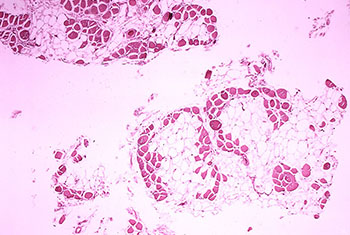

The stromal vascular fraction of adipose tissue is known to contain mesenchymal stem cells, T regulatory cells, endothelial precursors cells, preadipocytes as well as anti inflammatory M2 macrophages. Safety of autologous adipose tissue implantation is supported by extensive use of this procedure in cosmetic surgery, as well as by ongoing studies.